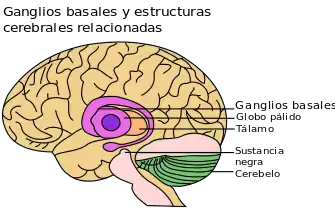

Estriado y ganglios basales

El estriado dorsolateral está relacionado con la adquisición de hábitos, y es el principal núcleo de células cerebrales relacionado con la memoria procedimental. Las fibras nerviosas aferentes conectoras participan en la regulación de la actividad del circuito de los ganglios basales. En esencia, existen dos rutas de procesamiento paralelas que parten del estriado, cada una de las cuales actúa en oposición a la otra en el control del movimiento, y que posibilitan la asociación con otras estructuras funcionales necesarias.[25] Una de las rutas es directa, mientras que la segunda es indirecta. Ambas trabajan conjuntamente como un bucle de retroalimentación neuronal. Existen muchos circuitos que llegan al estriado desde otras áreas cerebrales, incluida la corteza límbica (relacionada con el procesamiento emocional); el estriado ventral (relacionado con el procesamiento de recompensas) y otras importantes regiones motoras implicadas en el movimiento.[26] El principal circuito implicado en las habilidades motoras que forman parte de la memoria procedimental se conoce como circuito ganglio basal-tálamo-cortical.[27]

El estriado es una estructura única, ya que no presenta las neuronas activadas por el glutamato que se encuentran en la mayor parte del cerebro. En cambio, se caracteriza por una alta concentración de un tipo especial de célula inhibidora productora de GABA denominada "neurona de proyección espinosa media".[28] Las dos rutas paralelas mencionadas anteriormente entran y salen del estriado y están formadas por el mismo tipo de neuronas especiales de proyección espinosa media. Estas neuronas son sensibles a diferentes neurotransmisores, y contienen una variedad de sus correspondientes receptores, incluyendo receptores de dopamina (D1 y D2), receptores muscarínicos (M4) y receptores de adenosina (A2A). Las interneuronas separadas se comunican con las neuronas espinosas del estriado en presencia de la acetilcolina, un neurotransmisor del sistema nervioso somático.[29]

El actual entendimiento de la anatomía y la fisiología cerebral sugiere que la plasticidad neuronal del estriado es lo que permite a los circuitos ganglio basales comunicarse con otras estructuras y participar funcionalmente en el procesamiento de la memoria procedimental.[30]